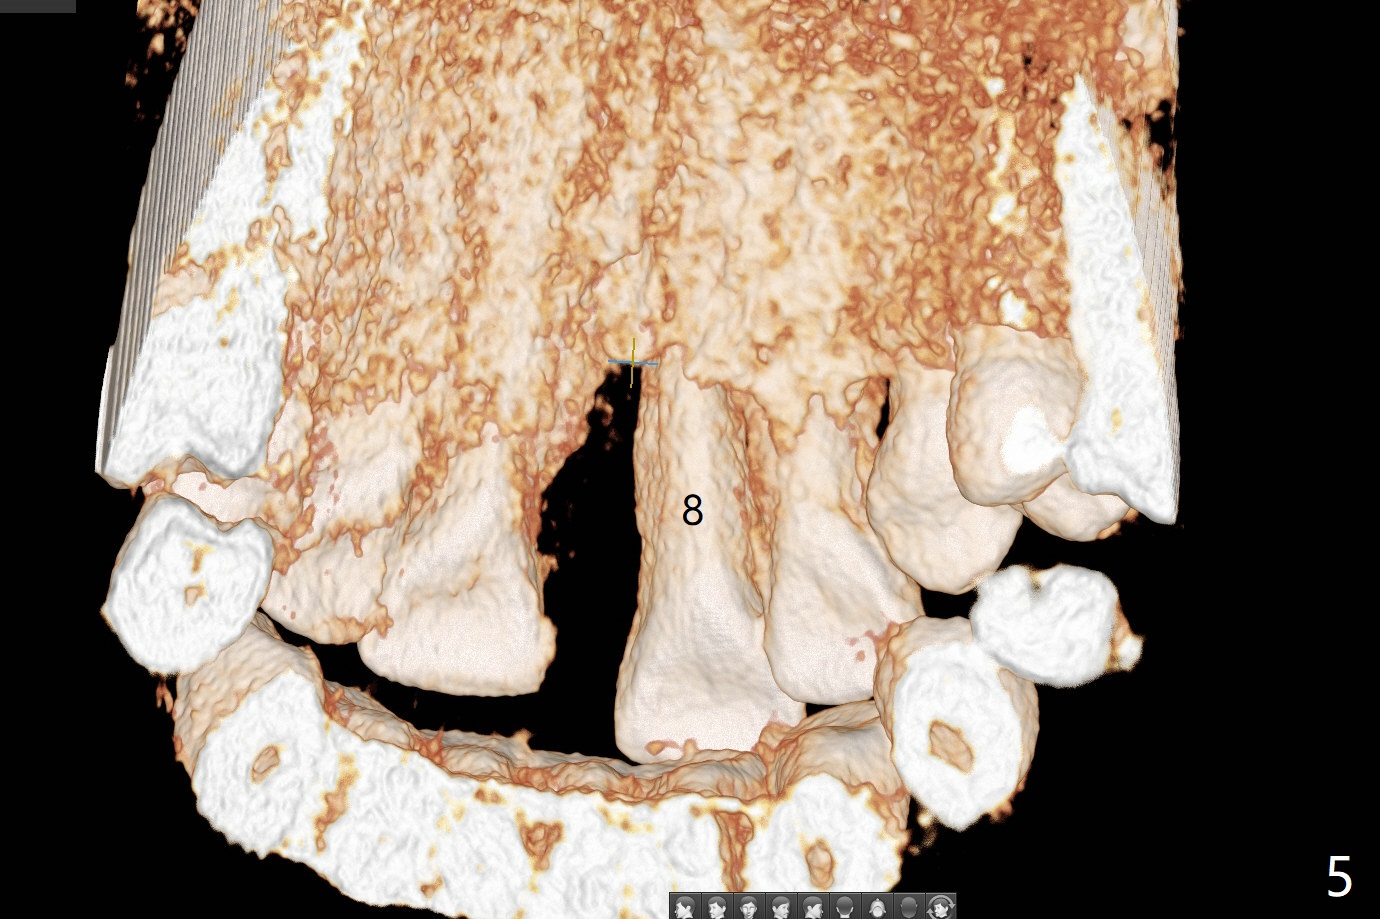

A 50-year-old woman complains of #8 buccodistal shifting (Fig.1,2). Conduct occlusal equilibrium until the affected tooth returns to its normal position. Trim the crown shell of the extracted tooth subgingival to the tooth #9 as a temporary crown (Fig.3,4). The gap between the socket and the tooth shell will be filled with sticky bone and PRF and covered by periodontal or acrylic dressing. The palatal bone loss is also severe (Fig.5); PRF should cover the palatal defect following sticky bone with a hole over the abutment.